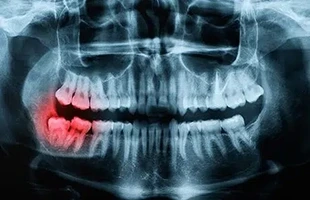

Gum Surgery Explained: Healing, Benefits, and Recovery Tips

Healthy gums are essential to maintaining strong teeth and a confident smile. Unfortunately, many people face gum-related issues like periodontal dise